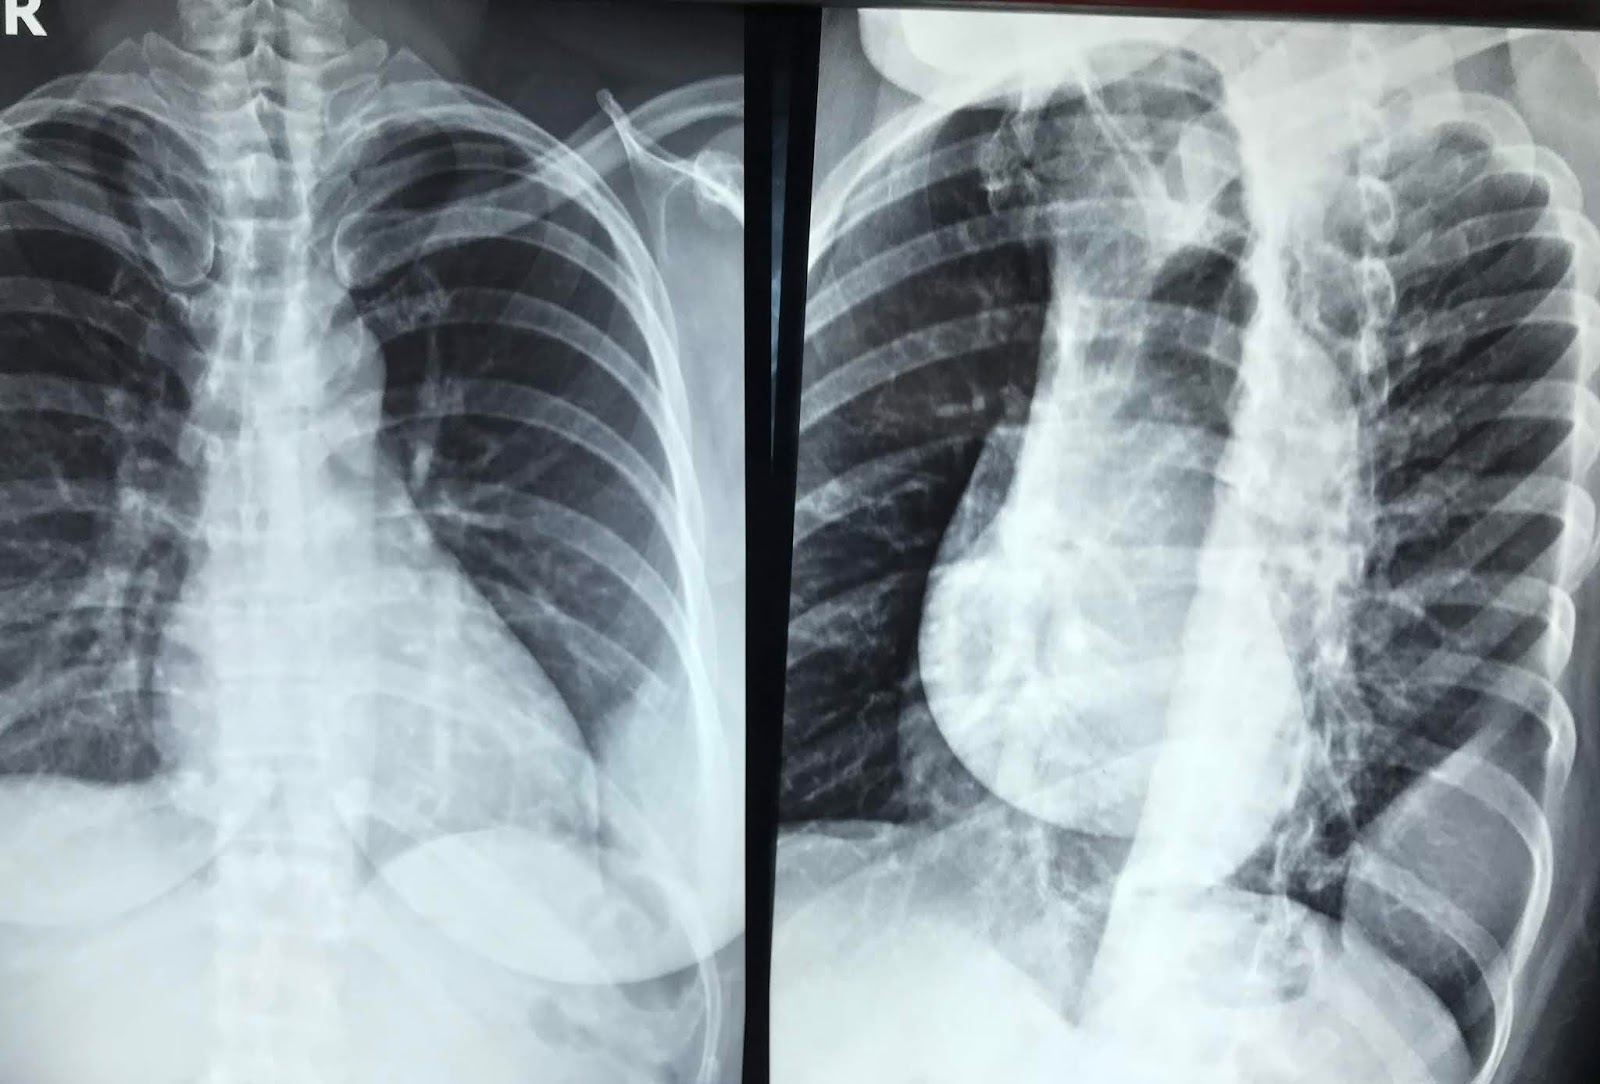

Chest x ray showing tumor of 6 th rib on right side Download Rib Cage Tumor tumors that are made up of cartilage or bone often cause pain, swelling, and impaired movement. the prevalence of tumors of the rib bones ranges from 3 to 8% depending on the series [1], [2]. These cancers can be benign or malignant. chest wall cancer is a tumor of the bone, cartilage, or soft tissue that makes. Rib Cage Tumor.